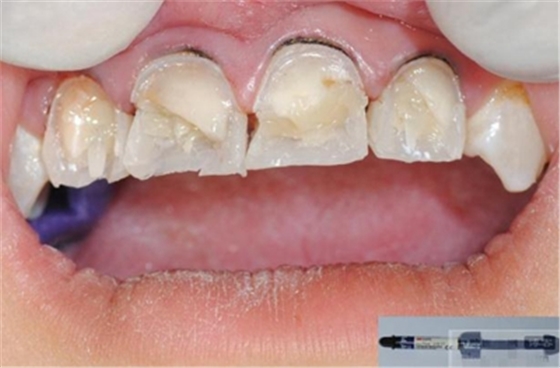

【分層堆塑】

A4本質(zhì)堆塑

A3本質(zhì)堆塑

發(fā)育葉制作

白堊斑

切端琥珀色制作

A3頸部堆塑

涂布防氧化劑

充填初步完成